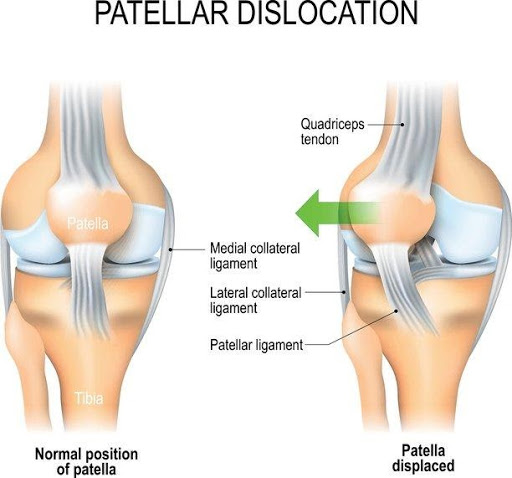

- The static stabiliser includes passive structures such as the knee joint capsule and the various ligaments and other associated structures such as the

- ligaments which all act as static stabilisers include the medial collateral ligament, the lateral collateral ligament, the ACL, PCL,

Vastus Intermedialis and the third is the Vastus Medialis Oblique. Each of these muscles attaches onto the patella and has its own direction of pull. The VL pulls the knee cap laterally (to the outside), while the VI pulls the knee cap directly upwards. The VMO, meanwhile, pulls the patella medially (to the inside).

Vastus Intermedialis and the third is the Vastus Medialis Oblique. Each of these muscles attaches onto the patella and has its own direction of pull. The VL pulls the knee cap laterally (to the outside), while the VI pulls the knee cap directly upwards. The VMO, meanwhile, pulls the patella medially (to the inside).